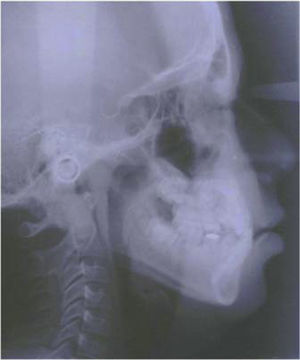

Un cefalograma fue hecho en oclusión céntrica así como los análisis cefalométricos de Steiner, Jarabak y Ricketts (Cuadro I).

De acuerdo con el análisis de Steiner, los ángulos SNA 84°, SNB 81°, ANB 3° indican una clase esquelética I biprotrusiva, el ángulo mandibular 34° indica un ligero crecimiento vertical mandibular. En relación con el análisis de Jarabak, la altura facial anterior (AFA) 110mm en norma y la altura facial posterior 73mm indican también un crecimiento vertical posterior mandibular. Respecto al análisis de Ricketts, la profundidad facial 84° en norma, profundidad maxilar 87° en norma 90° ± 3°, convexidad 3mm indicando clase esquelética I biprotrusiva, altura facial inferior 49°, cono facial 66°, plano mandibular 32°, arco mandibular 29° y eje facial 90° registran un crecimiento ligeramente vertical de la mandíbula. En los tres análisis, los incisivos maxilares se registraron retrusivos y retroclinados, contrario a los incisivos mandibulares que se encontraban en una posición normal sobre su hueso basal: análisis de Steiner ángulo 1aNa 10°, distancia 1aNa 1mm, ángulo 1aNB 25°, distancia 1aNB 8mm. Análisis de Jarabak ángulo SN/1 sup 94°, ángulo Go/Gn 1 inf 90°, ángulo interincisal 142°.

El labio superior, en relación con la línea estética, se encontraba en una posición retruida y el labio inferior en protrusión. El ángulo nasolabial estaba aumentado por el poco soporte labial que ofrecían los centrales superiores (Figuras 1 a 5).